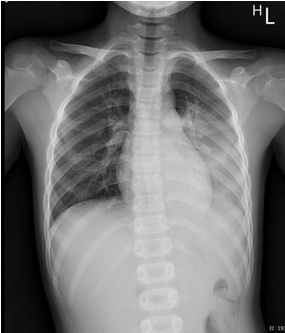

右圖:一名八歲男童因呼吸道融合病毒(RSV)合併肺炎鏈球菌及鼻病毒的感染,造成左側大葉性肺炎,胸部X光照片顯示左邊肺部位置幾乎變白了。

一名八歲男童因呼吸道融合病毒(RSV)合併肺炎鏈球菌及鼻病毒的感染,造成左側大葉性肺炎,就醫檢查胸部X光發現左邊肺部幾乎白了,住進花蓮慈院兒科加護病房接受治療。陳明群主任指出,在過去的兒科臨床案例中,這種RSV造成年紀較大的孩子發生肺炎的案例是相對少見的,大多都是四五歲以下的小小孩免疫系統還未成熟且細支氣管較細小,被病毒攻擊時才會這麼嚴重。陳明群舉例,一般兒童原本會在成長過程中偶爾得到小感冒,讓體內的免疫系統循序漸進、慢慢累積對疾病的抵抗力,這是身體自然建立防禦的過程;但過去三年間孩子們被保護得很好,戴口罩、勤洗手、保持社交距離等防疫措施更大幅隔絕飛沫傳染細菌及病毒的可能,因此當解除防疫限制後,身體一下子接觸到多種從未碰過的病毒,就像許多小感染的威力一次聚集發作,造成比普通感冒更為嚴重的症狀,即「免疫負債」效應,讓即便已上小學年紀的孩子也難免除於多重呼吸道細菌及病毒的攻擊。